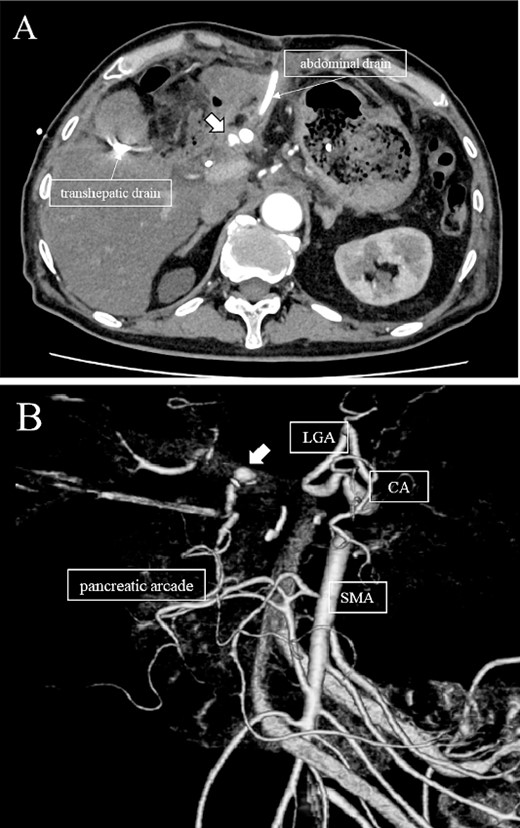

Subsequently, interventional radiology (IVR) was performed. However, because the inferior pancreaticoduodenal artery (IPDA) was very narrow, the microcatheter could not be followed, and hemostasis with IVR was difficult. Therefore, on POD 48, relaparotomy pseudoaneurysm repair was performed. The abdomen was opened through an inverted L-shaped incision, and adhesiolysis was performed, after which a pseudoaneurysm was revealed at the junction of the GDA and PHA. Four transfixing sutures with 3–0 prolene were used. After confirming that the liver blood flow was maintained, surgery was completed. However, bloody drainage from the drain was observed on POD 56. CeCT revealed a pseudoaneurysm (Fig. 3A and B). IVR was considered difficult because of the narrow blood vessels; therefore, the patient underwent a second laparotomy for hemostasis. A pseudoaneurysm was further observed at the junction between the GDA and PHA. In this operation, we used deeper and wider penetrating sutures than in the previous surgery to completely halt blood flow in the GDA. We confirmed that the blood flow to the liver was maintained; however, it was deemed weak. The patient had an uneventful postoperative course without bleeding, and CeCT performed on POD 61 confirmed the disappearance of the pseudoaneurysm. Although the blood flow in the PHA could not be confirmed, the right and left hepatic arteries were preserved (Fig. 4). On POD 76, CT revealed no liver abscesses or infarctions. The drain was removed on POD 78, and the patient was finally discharged on POD 107 without rebleeding or liver failure.

(A, B) CT on postoperative Day 56. Contrast-enhanced CT shows a pseudoaneurysm at junction of the GDA and PHA (arrow).